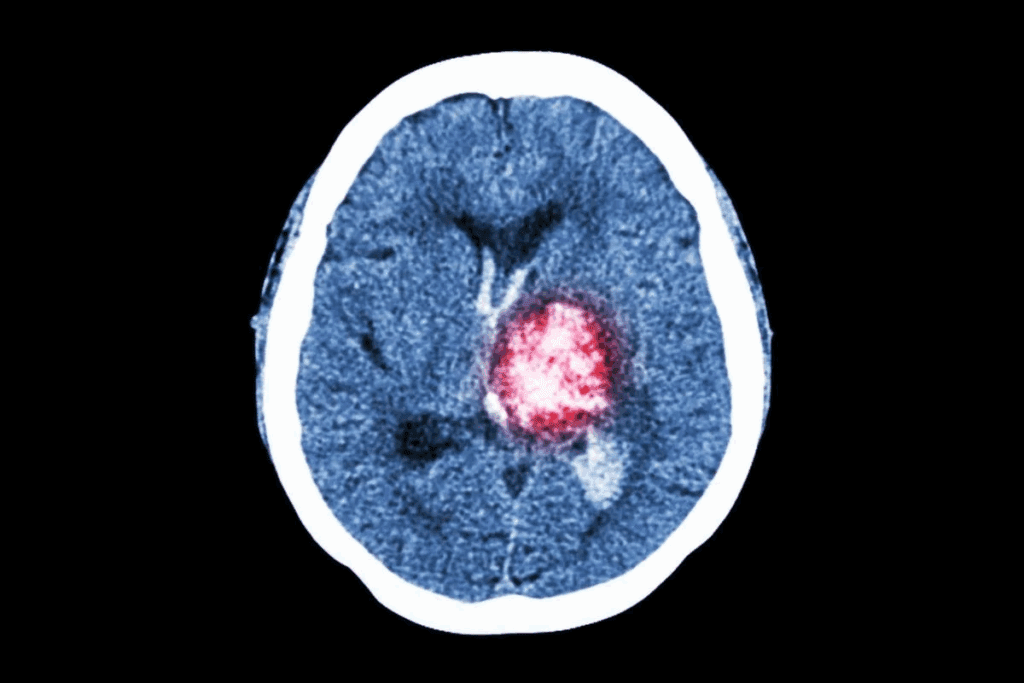

Doctors use MRI or CT scans, along with checks of the nervous system and sometimes a biopsy to find brain tumors. Finding them early is key to treating them well.